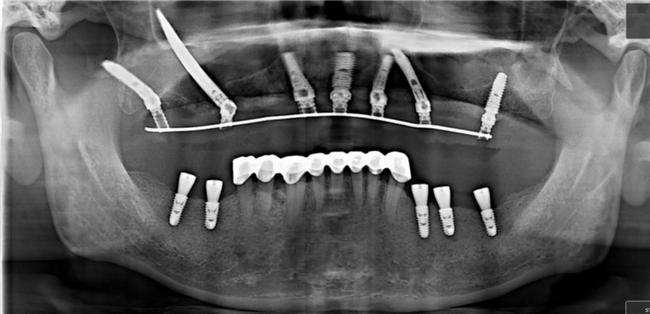

今年年初,刘昭遇到了一位特殊患者:骨量极差,却坚持 “当天有牙、不植骨、不延期”。这正是穿颧种植的 “拿手好戏”,他第一时间把方案发给强总,很快收到了详细的指导意见。

“本来想请强总现场指导,可他太忙了,全国飞。最后决定远程‘托底’,我来主刀。” 手术当天,刘昭回忆着跟强总配台时学到的细节,按照方案一步步操作 —— 钻骨、植入、固定基台…… 整个过程 “比预想中更顺”。

术后,患者当天就戴上了牙,对着镜子笑了又笑:“真没想到这么快!” 刘昭把术后 CT 发给强总,收到的回复是 “位点不错,细节还能再优化”。这句点评,既是肯定,更是鞭策。而这个案例,也成了 2025 年大湾区首例穿颧穿翼即刻负重案例。“广东做穿颧手术的医生少,案例也少,能让患者在家门口解决难题,比什么都开心。”